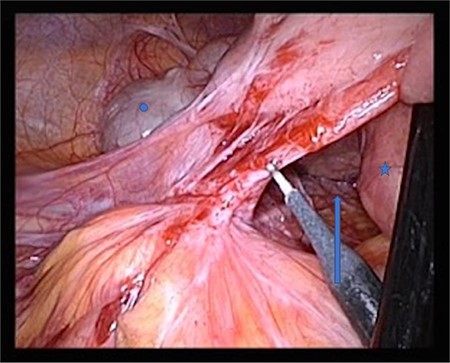

The patient was positioned supine. We used a 12-mm umbilical camera port, and 5-mm trocars were placed in the left and right middle abdomen. Laparoscopic inspection revealed a hernia aperture below the terminal ileum, behind which we found the hernia sac where the small intestine had become entangled 3 weeks previously (Fig. 3). The subsequent small bowel revision was uneventful. In the area of Treitz’s ligament, the vessels were on the right side with no herniation on the left side (Fig. 4). At this point, we decided to enlarge the hernia aperture by mobilizing the cecum. The ureter and the testicular vessels were identified. Finally, the hernia sac was widened, to prevent future entrapment of the small intestine. (Fig. 5) The postoperative course was uneventful and the patient was discharged 2 days later.

Both pictures display the hernia sac; in the right panel, the hernia sac has been elevated. Circle: terminal ileum, cross: appendix, star: ureter, triangle: V. cava, arrow: hernia sac, which has been opened